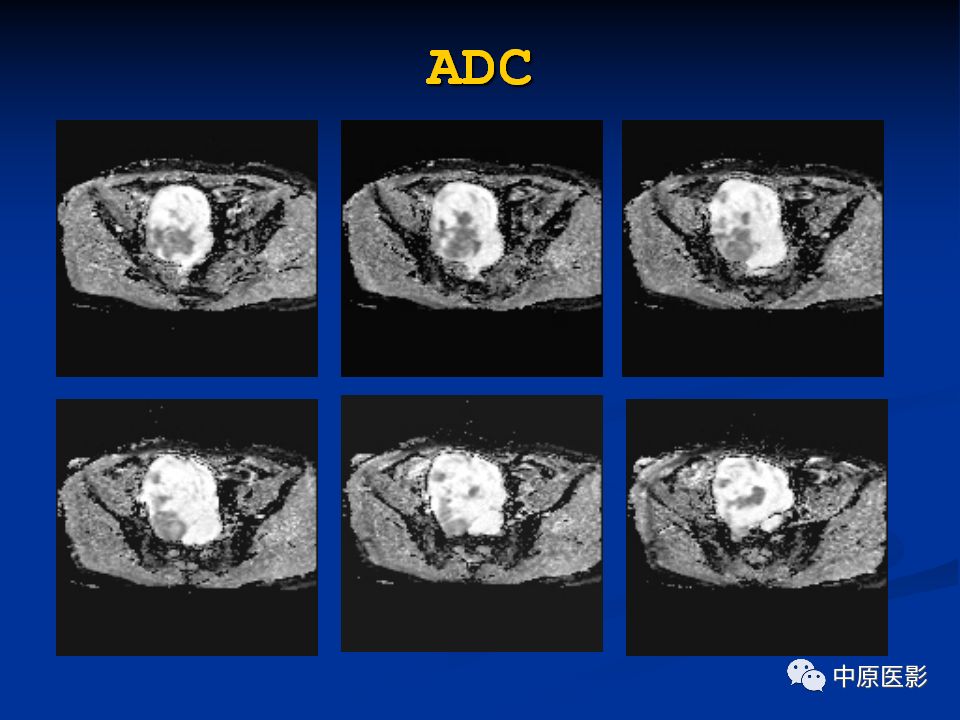

腹膜后盆腔神经鞘瘤1例MR影像